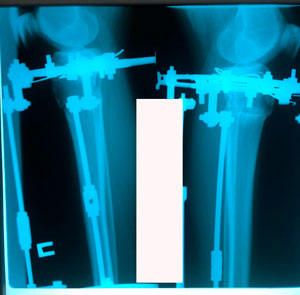

Пациентка - 37 лет.

Диагноз: варусная деформация голеней. Ротация с обеих сторон.